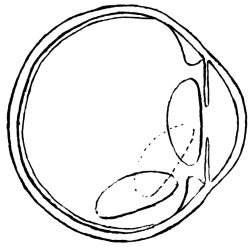

The introduction of reclination, as opposed to depression, by Willburg in a Nuremberg thesis, dated 1785, gave a fresh lease of life to couching in its dying struggle with the operation which was destined to supersede it. England, France, Sweden, Germany, and other countries, joined vigorously in the discussion, and amongst the powerful advocates of couching were ranked Percival Pott and William Hay of London, Cusson of Montpellier, and Scarpa of Pavia, whilst Benjamin Bell practised both couching and extraction. The admirable treatise by James Ware on cataract (1812) was all but a death-blow for Celsus’s operation. The newer procedure was then well in the ascendant, and only needed time to completely strangle its rival. Notwithstanding this, it was left to Mackenzie, so late as 1854 (fourth edition), to give the most complete and interesting description of couching to be found in literature. He distinguishes sharply between the operations8 of depression and reclination. In depression, the lens is pushed directly below the level of the pupil, being made to follow the curvature of the eye, to sweep over the corpus ciliare, until it comes to rest on the lower curve of the eyeball, with its anterior surface directed forward and downward (Fig. 3). In reclination, the lens is made to turn over towards the bottom of the vitreous chamber in such a way that what was formerly its anterior surface now comes to look upward, and what was its upper edge is turned to the rear. The whole lens is swung backward as if on a hinge, composed of the lower fibres of its suspensory ligament, which still remain unbroken (Fig. 4).

Fig. 5.

He divides the operation of couching into four stages, in only the last of which reclination differs from depression. These are: (1) the pushing of a special needle (Fig. 5) through the coats of the eye at a distance of 1/6 inch behind the temporal edge of the cornea, and to a depth of 1/5 inch; (2) the laceration of the posterior capsule of the lens by vertical movements of the point of the needle, to prepare an aperture for the passage of the lens; (3) the passing of the needle into the anterior chamber around the edge of the lens, and the laceration of the anterior capsule by vertical strokes; (4a) to depress the lens, the point of the needle is carried over its upper edge, and the handle is9 raised a little above the horizontal, thereby correspondingly lowering the point, which forces the cataract downward out of sight behind the pupil: the needle is then withdrawn by rotation; (4b) to effect reclination, the needle-point is raised not more than 1/10 inch above the transverse diameter of the lens: its concave surface is pressed against the cataract, which is reclined by moving the handle of the instrument upward and forward, thereby causing its point to pass downward and backward. The cataract is thus made to fall over into the vitreous humour, and is then pressed downward, backward, and a little outward. Mackenzie adds many interesting details as to the modifications of the operation, according to the variety of the cataract to be dealt with, and as to the after-treatment and complications met with.